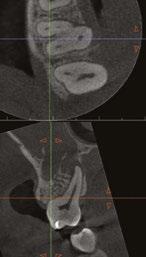

On a recent second molar case where I did not take a 3D scan prior to root canal treatment, the patient returned several days later still in pain! I took a scan and appreciated their deep split, forked in the last 5 mms of the distal canal (Figure 8). Without a CBCT scan, it’s easy to miss — I did! CBCT helps prevent this from happening by catching those variants and hard-to-find issues, which are not as rare as we think. This was another case that helped shape my current imaging protocol, so that now I scan nearly all of my patients. I honestly can’t imagine practicing without my CBCT unit — similar to when the microscope was introduced to endodontics.

Figure 7: Planned-for access with the scan info on this extremely calcified canine Figures 8 and 9: 8. Deep distal split with PARL. 9. Missed buccal canal; history of previous RCT, post, crown and apico Figure 10: Retreatment consultation. PA from GD Figure 11: Scan images show a previously existing strip perforation

what the literature suggests. And, when I know how many and where the canals are (Figure 13), I can take measurements on the scan and work more efficiently — measuring my working lengths of each canal, appreciating severe curves or calcifications, and knowing where canals can be expected to be located, again, rather than removing unnecessary tooth structure to find if it is there, or not!

As an endodontist, I often treat heavily restored teeth. I am often planning my accesses based on the scan’s information. This saves time and conserves more tooth structure. I’m not looking for canals that may or may not be there, and I’m looking for canals under the targeted/planned access — with the scan, I have an actual map (Figure 7)! CBCT directs me where to go and where to end. It reveals anomalies, which are more common than we think, so I can avoid iatrogenic incidents and provide less invasive treatments. Lower second molars with only two canals occur — often!

I’m also changing my treatment plans based on the data from my CBCT. Sometimes I look at a root canal treated PA and presume I know what I will do: a retreatment or an apico. Another recent, poignant case: a lower incisor with a previous RCT and a previous apico (Figure 9). Usually, once a tooth has had an apico, there may not be much left to offer and most of the time, the default is another apico, especially as there was very little room for an implant on the lower anteriors. I scanned the tooth and saw that a whole canal had been missed — twice! The RCT and the apico had left the buccal canal completely untouched. I changed my treatment plan based on this information!

Cracked teeth are also quite prevalent (Figure 12). Of course, I can suspect them clinically and with transillumination and other tests, I’m fairly confident in my diagnosis. Thankfully, the 3D scan proves it and shows the depth of these cracks and the angular defect. Without a CBCT, sometimes these cases are started unnecessarily.

Lastly, using CBCT also allows me to find issues that should be evaluated by another specialist. For example, when I capture incidental sinusitis, I can inform my patient to see an MD or ENT and can provide the 3D images to share with their physicians; or, to involve another dental specialist. (Figures 2, 4, 6, and 11 show incidental sinus findings.)

Figure 12: Cracked tooth Figure 13: Five canaled maxillary molar with five portals of exit